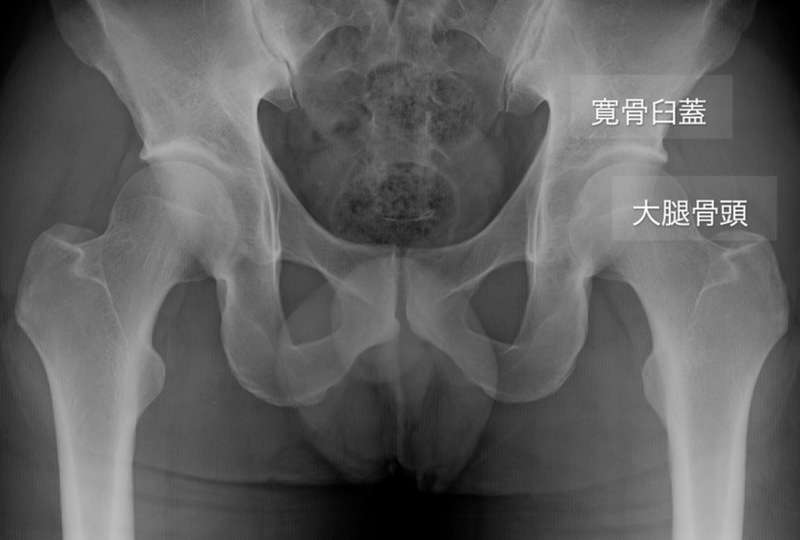

大腿骨寛骨臼インピンジメント(以下FAI)は股関節痛の原因の1つで股関節唇損傷、軟骨損傷、早期の変形性股関節症の原因と考えられています。

FAIは大腿骨頭・頚部と寛骨臼蓋縁との間の繰り返される衝突(インピンジメント)により関節唇や関節軟骨の損傷が起こります。関節内の損傷が進むと関節症性変化(OA変化)を起こすことが知られています。